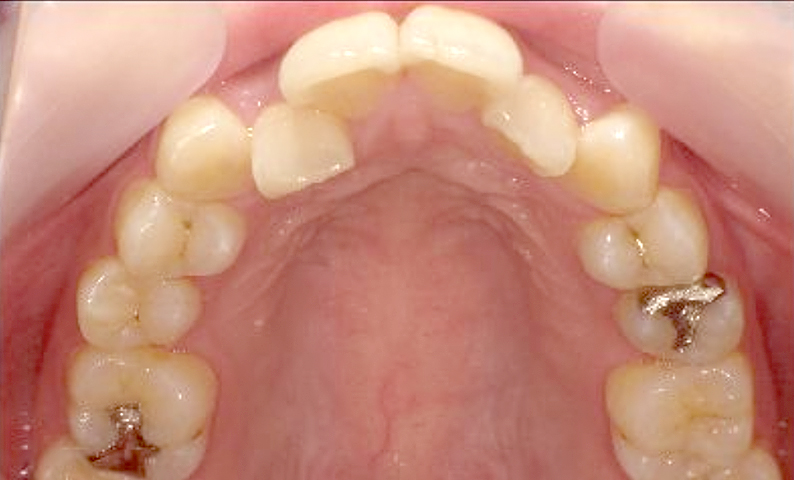

症例_025 上下顎の部分矯正

治療期間:13ヶ月金額:51万円+税女性前歯のガタガタ出っ歯

| Before | After |

|---|---|